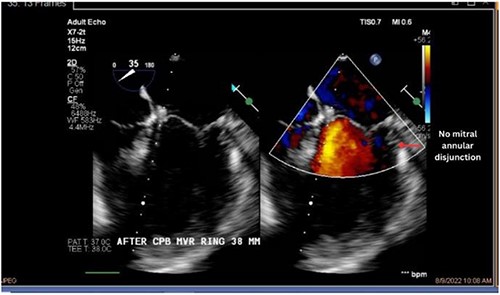

Both sisters underwent a minimally invasive procedure through a right-sided lateral minithoracotomy performed at the level of the third or fourth intercostal spaces. Cardiopulmonary bypass was established through a femoral access and cardioplegic cardiac arrest was achieved through a modified Del Nido solution (20 ml/kg). Mitral valve repair was performed through isolated annuloplasty using in both cases a 38-mm semi-rigid annuloplasty ring. Transesophageal echocardiography after repair revealed excellent surgical results, with no rest regurgitation, no SAM of the mitral valve and most importantly no detectable mitral annular disjunction (Figs 7 and 8). In both cases, being performed several months apart, the patients were extubated in the operating room and transferred to our ICU for further observation.